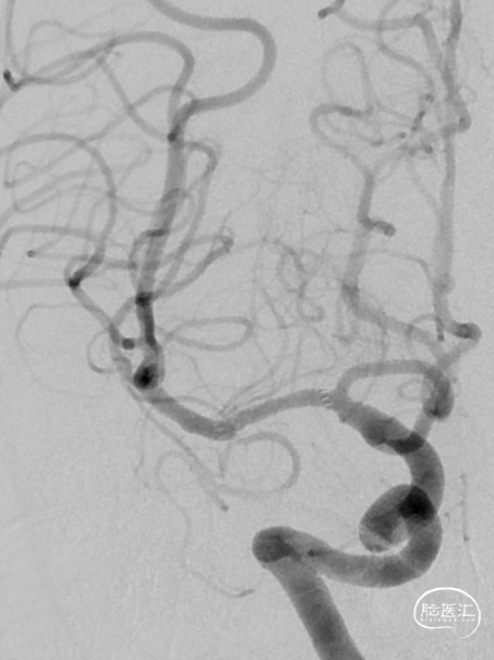

造影见RICA再通,RMCA M1段近端重度狭窄,约90%。

观察10分钟后,狭窄较前加重,局部不规则充盈缺损。术中即刻DynaCT未见造影剂染色。

将Synchro(0.014×300cm)微导丝外衬Gateway(2.0×15mm)球囊缓慢通过RMCA M1段狭窄处,球囊定位于RMCA狭窄处缓慢扩张,压力6atm。采用交换技术置入灌注微导管,并将4.0×16mm支架定位于狭窄处释放。

复查造影见支架展开良好,支架内及远端血流通畅,TICI分级3级。术顺,术毕,Proglide缝合术口。